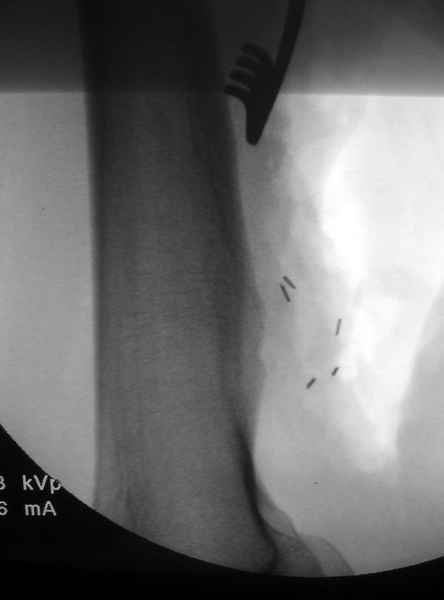

Ангиография подтвердила васкулярную аневризму в

результате давления экзостозом. Совместно с сосудистым хирургом была проведена плоскостная резекция с дальнейщим восстановлением сосуда венозным графтом.